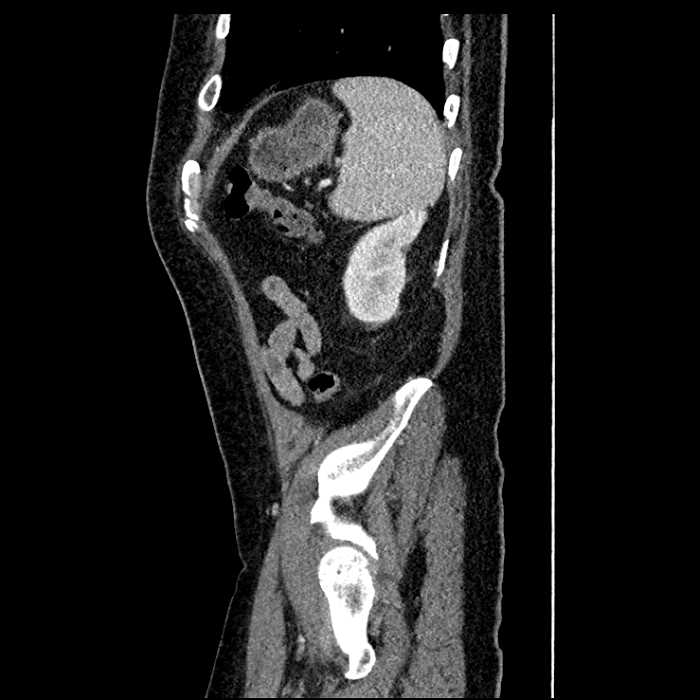

• Large fluid density structure in hepatic segments 7 and 8 measuring 10 x 7 x 7 cm with internal septation and circumferential ill-defined low density compatible with edema

• Peripherally enhancing subcapsular collections along the anterior margin of the left hepatic lobe measuring 3 x 1 cm and 2 x 1 cm

Acute sigmoid diverticulitis complicated by a small contained perforation and a large abscess in the right hepatic lobe. Additional small subcapsular abscesses along the anterior margin of the left hepatic lobe.

• The classic CT imaging appearance is a double target sign with internal low density surrounded by an internal enhancing rim (capsule) and a low density external rim (edema)

Hepatic abscess showing the double target sign with low density internally surrounded by a thin inner enhancing rim (red arrow) and ill-defined outer low density rim (yellow arrow). Blue arrow indicates an internal septation. Red arrows: additional smaller subcapsular abscesses. Red arrow: focal contained perforation associated with diverticulitis.